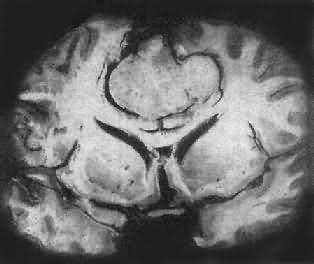

高度恶性的星形胶质细胞称为多形性胶质母细胞(glioblastoma multiforme),多见于成人。肿好发于额叶、颞叶白质,浸润范围广,常可穿过胼胝体到对侧,呈蝴蝶状生长(图16-24)。体因常有出血坏死而呈红褐色。镜下,细胞密集,异型性明显,可见怪异的单核或多核巨细胞。出血坏死明显,是其区别于间变性星形胶质细胞的特征。毛细血管明显增生,内皮细胞增生、肿大,可导致管腔闭塞和血栓形成。肿发展迅速,预后极差,患者多在2年内死亡。

图16-24 多形性胶质母细胞

在两半球内肿呈蝴蝶状,边界不清,切面见有出血、坏死及液化